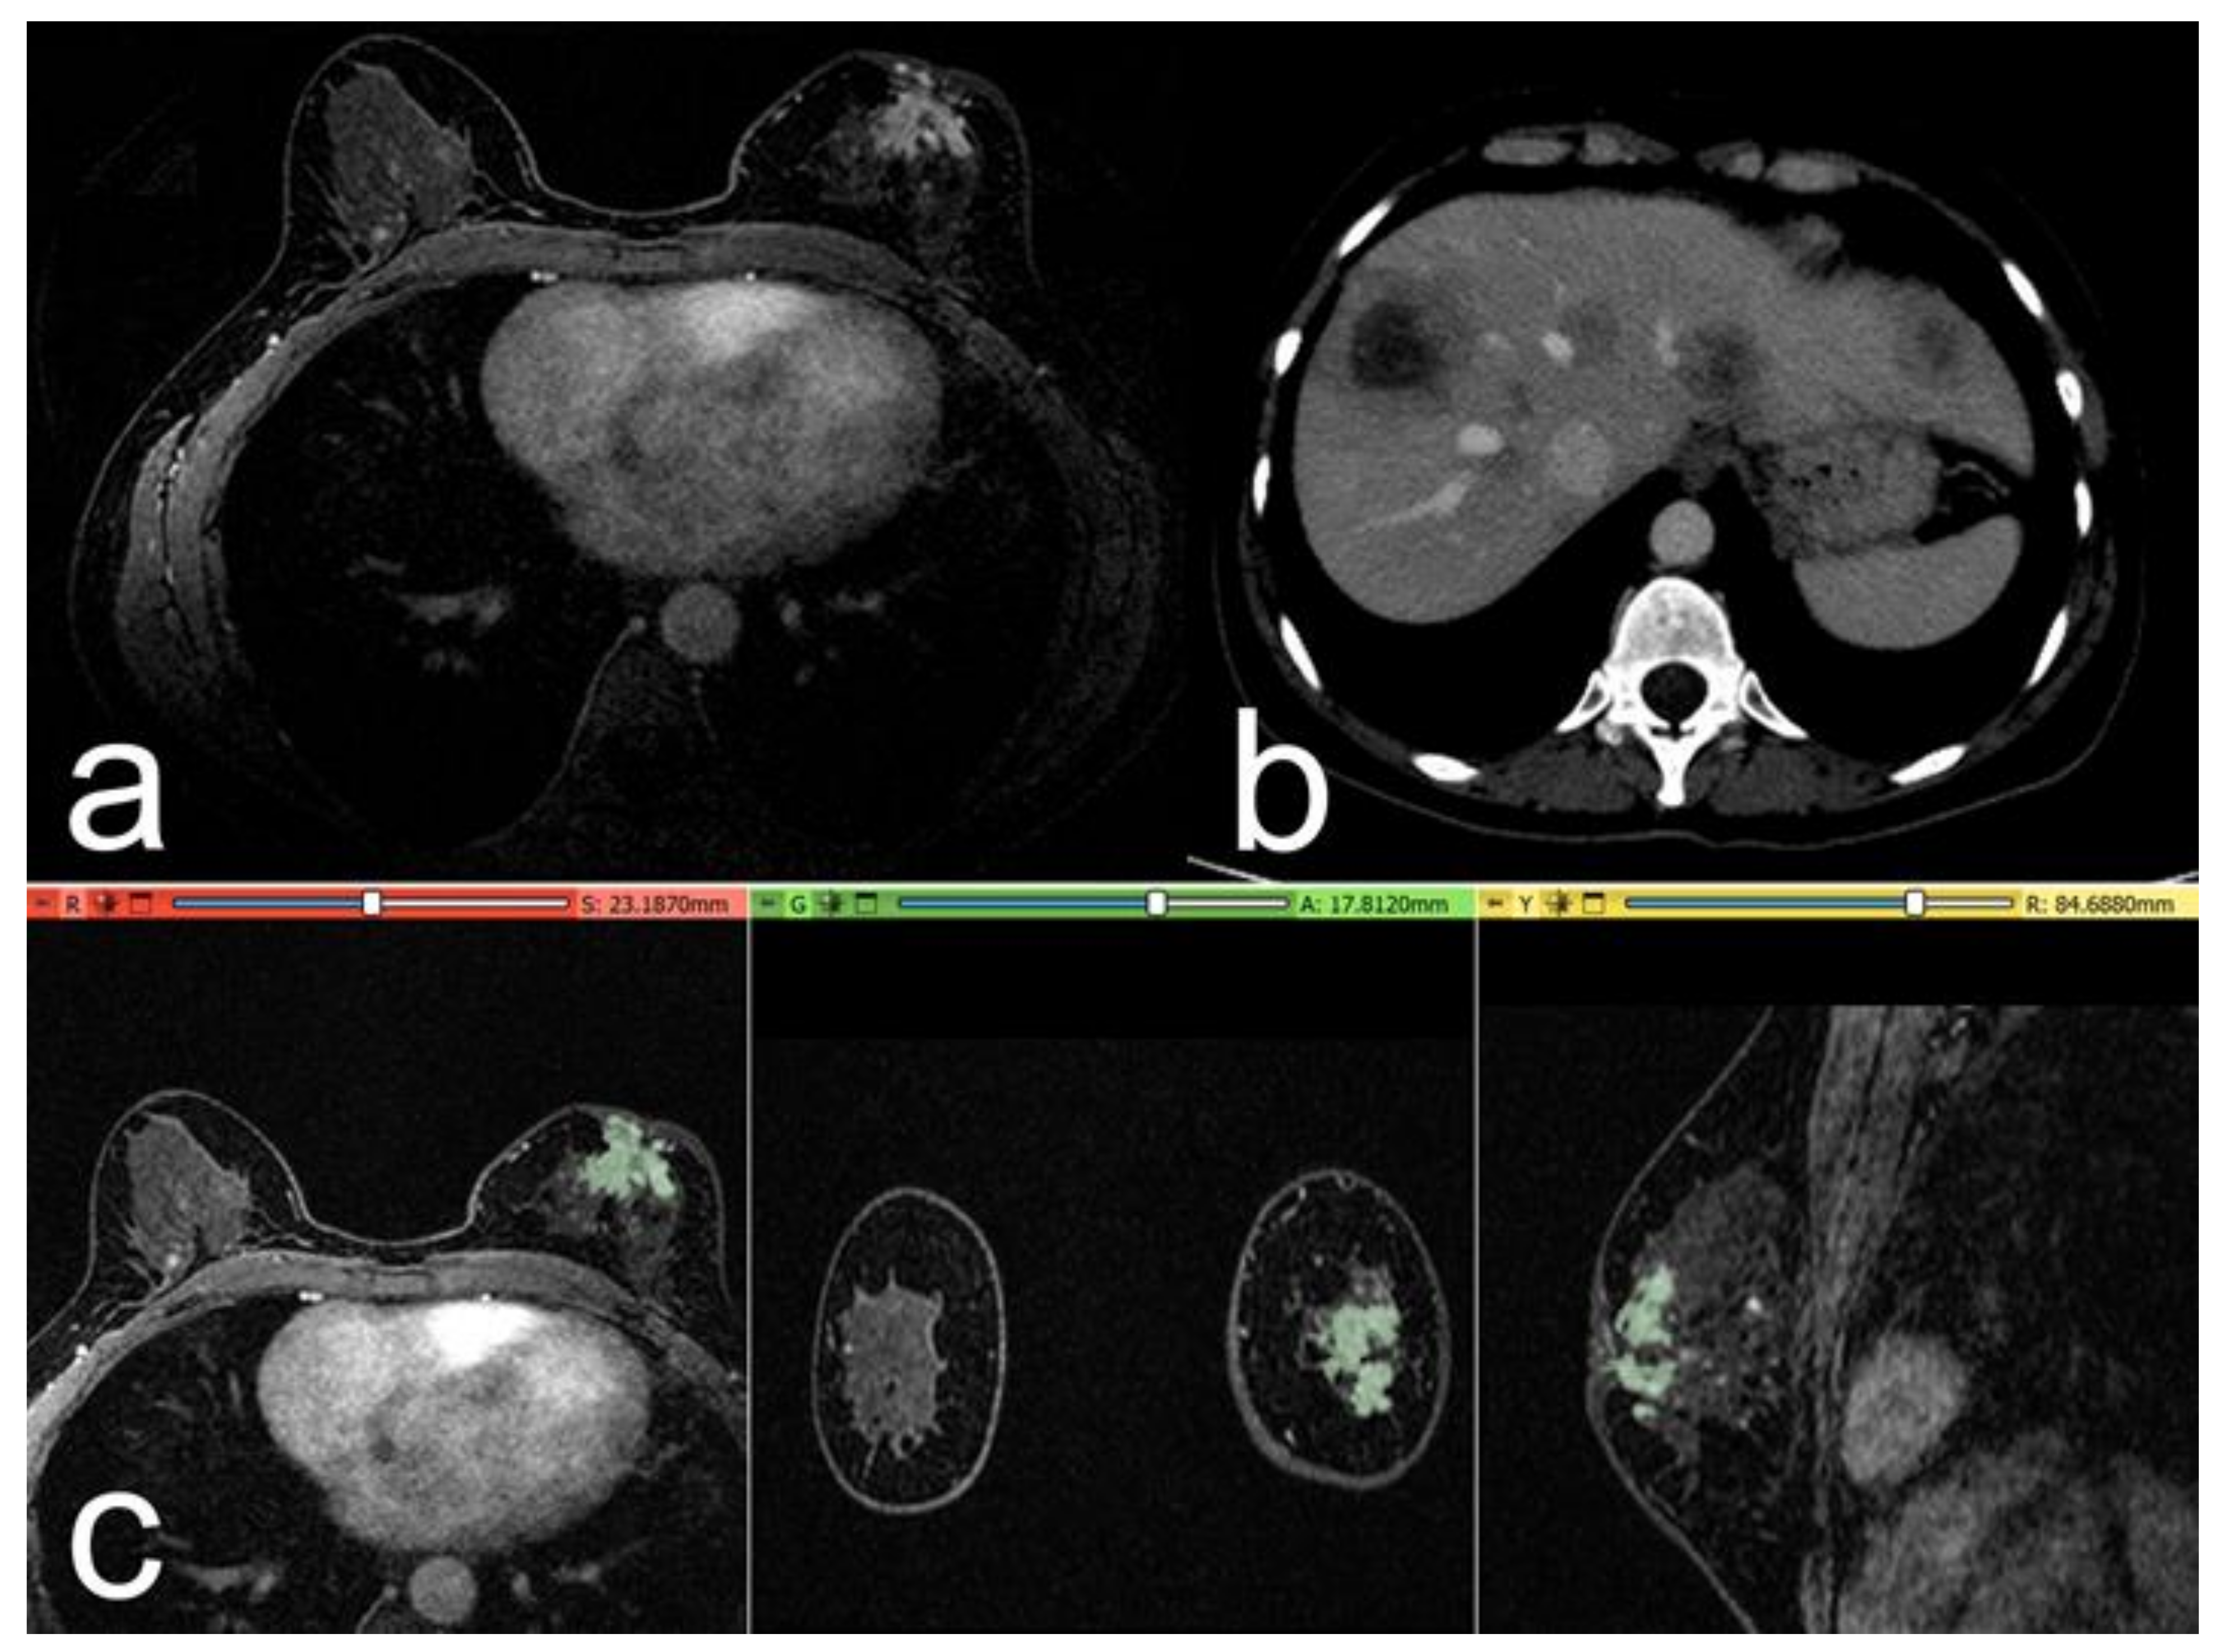

2.4. Segmentation and Pre-Processing

2.5. Volumes Extraction

2.6. Metastasis Prevision Assessment

3. Results